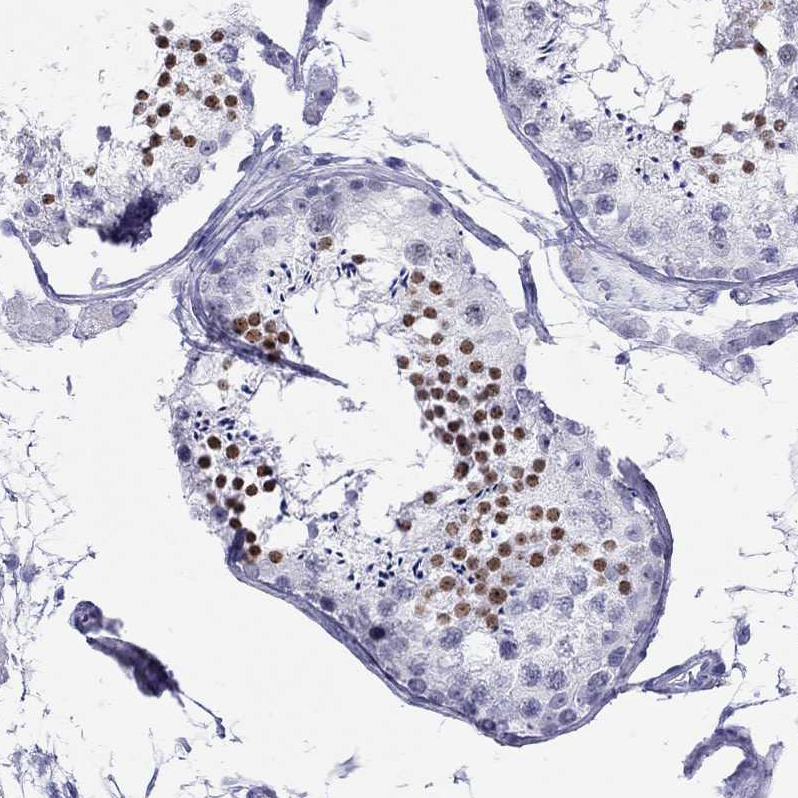

Immunohistochemistry analysis in human testis and fallopian tube tissues using HPA035881 antibody. Corresponding LYAR RNA-seq data are presented for the same tissues.